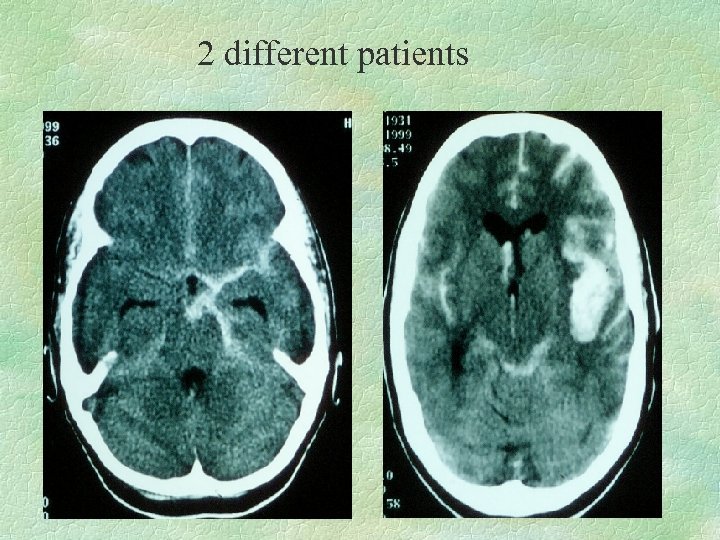

2 different patients